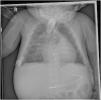

The patient was treated with prostaglandins through age 5 months, at which time she underwent heart transplantation. Six months later, hyperostosis persisted in the follow-up imaging tests (Fig. 3).

Plain radiographs taken after heart transplantation and at the end of treatment with prostaglandins. (A) At 3 months, (B) at 4 months, (C) at 6 months. They continue to show hyperostosis and bone thickening, without improvement or resolution after discontinuation of prostaglandin treatment. There seem to be no involvement of the pelvis or spine. The mandible was not affected either.